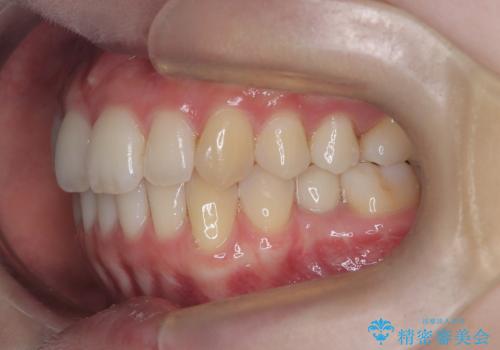

- 患者様は、前歯のガタガタ(叢生)と左下5番の欠損部が気になるとのことで来院されました。診断の結果、インビザラインを用いて前歯の叢生を整えながら、左下5番の欠損部にはインプラント治療を計画しました。矯正治療により、歯並びを改善すると同時に、噛み合わせのバランスも向上させることを目標としました。矯正期間とインプラントの治療計画を並行して進めることで、患者様のご希望に応えるプランを立てました。

前歯の叢生改善のため、インビザラインによる透明で目立たない矯正装置を使用しました。治療中は、歯の移動による負担を最小限に抑えつつ、歯列全体のバランスを考慮して進めました。左下5番の欠損部には、矯正終了後にインプラントを埋入し、自然で機能的な咬合を回復しました。治療期間中、患者様には装置の正しい装着と日々の清掃を徹底していただき、歯肉やインプラント周囲の健康を保つようサポートしました。結果として、美しい歯並びと快適な噛み合わせを両立させることができました。